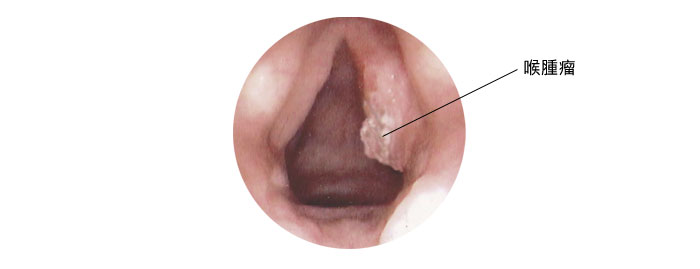

咽喉癌 楊永榮博士癌症資訊網